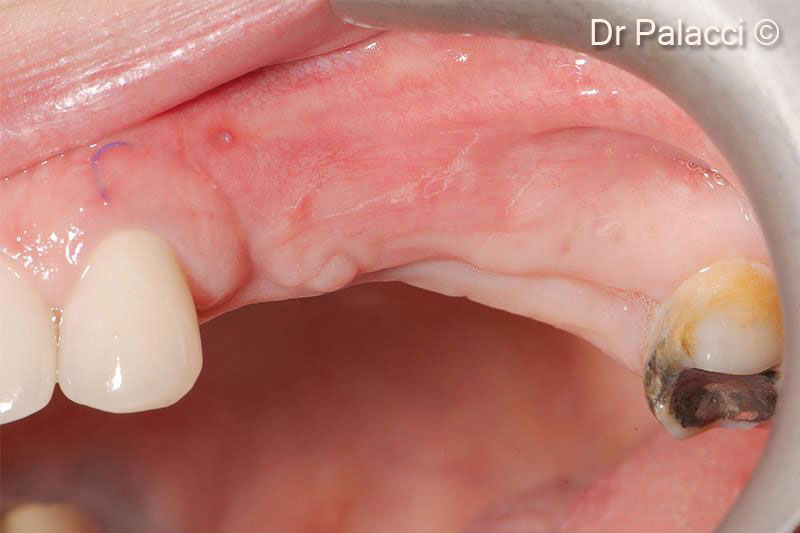

Tái khám sau 4 tháng. Lưu ý sự tăng thể tích đáng kể của sống môi cũng như chất lượng mô mềm

Lưu ý thể tích mô cứng tối ưu đạt được và chất lượng hình thành xương